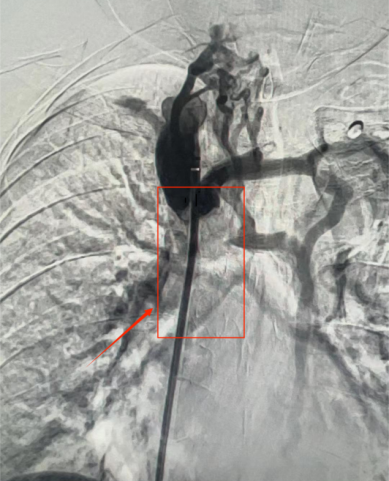

图片

球囊扩张联合支架置入恢复

上腔静脉通畅